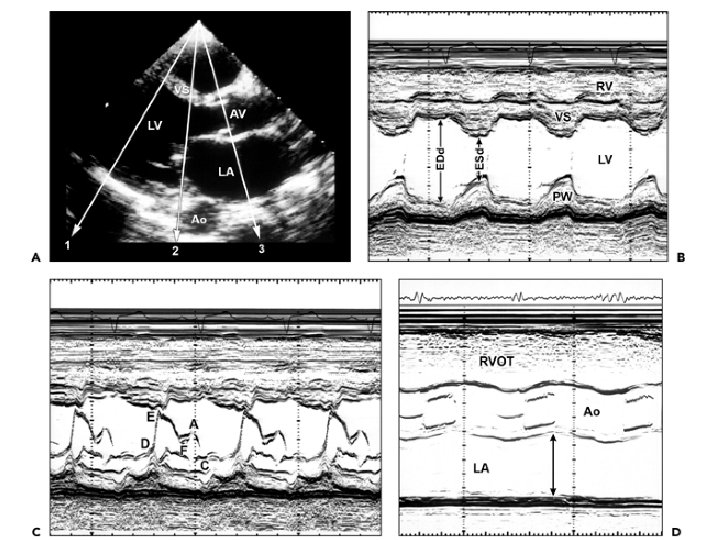

M – MODE SCAN